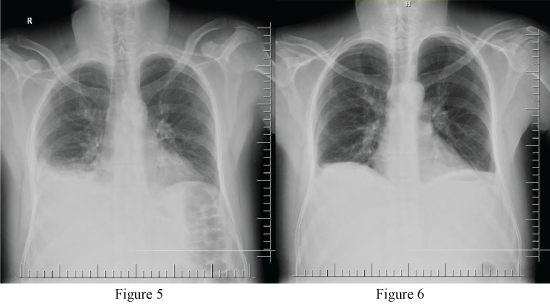

Patıent was operated after 2 days (nearly 50 hours) after he had been accepted to the hospital. During the exploration, 250 cc hemorrhagic collection was obresved in the abdomen, and it was aspirated. No signs of active bleeding were observed in laceration area in liver. Posterior of stomach was explored by openning gastrocolic ligament. Peripancreatic collection, ischemic foci and peripancreatic calcified fat necrosis were present in whole pancreas. However, major laceration area and necrotic regions were not detected in pancreas. Approximately 200 cc organized hematoma which was significant in paracaval and para-aortic region in retroperitonel field was observed. Hemostasis control was performed by draining hematoma. Upon absence of active bleeding, abdominal drain was placed to the patient, and the operation was ended. The patient was consulted on this stage about infectious diseases, and meropenem 3 × 1 g antibiotics was started. In post-operative follow-up, approximately 500 cc fluid per day came from right and left drains of the patienton post-operative day 1 (Figure 5). Upon presence of pleural effusion on the right in control PAAG of the patient with ongoing subfebrile fever post-operatively, the patient was consulted to the interventional radiology, thoracentesis was performed, and 300 cc serous transudate-qualified liquid was drained. After the thoracentesis it was seen in control PAAG that costophrenic recess blunt was lost (Figure 6).